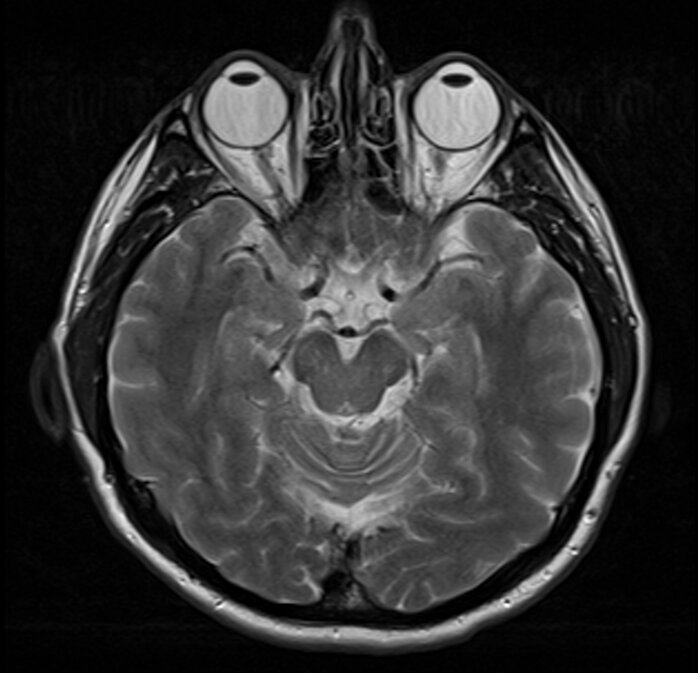

В ходе исследования ученые изучили данные магнитно-резонансной томографии (МРТ) 40 гетеросексуальных отцов, половина из которых проживает в Испании, а половина — в Соединенных Штатах, а также контрольную группу из 17 бездетных мужчин в Испании.

Отцы в Испании прошли сканирование мозга до беременности их партнерш, а затем еще раз через несколько месяцев после рождения ребенка. Мозг американцев сканировали на средних и поздних стадиях беременности партнерш, а затем снова через семь-восемь месяцев после рождения ребенка.

Затем исследователи сравнили данные с результатами контрольной группы и обнаружили признаки пластичности мозга в корковом сером веществе. Это область, которая отвечает за понимание социальных сигналов.

«Также мы обнаружили тенденции уменьшения объема коры головного мозга в default mode network и зрительных сетях, а также сохранение подкорковых структур в обеих выборках мужчин, которые стали отцами впервые», — пишут исследователи.